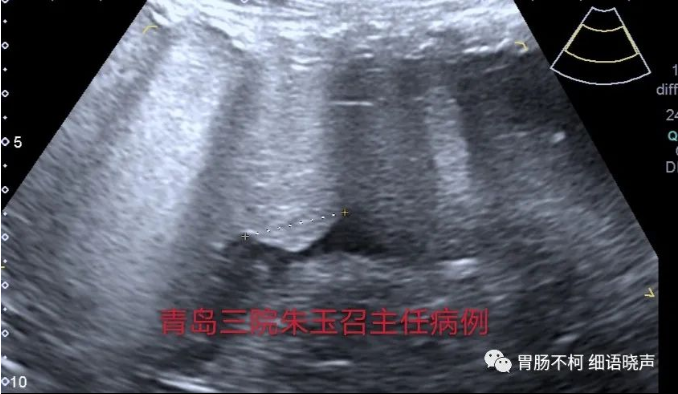

但在应用的时候,应注意不典型病例带来的鉴别困扰。比如胃壁因炎症水肿增厚明显,易导致良性溃疡与“土堆挖坑征”不易鉴别;浸润溃疡型胃癌的溃疡,易表现为“平地挖坑征”;愈合期溃疡与浸润溃疡型胃癌的鉴别有困难。无论典型不典型,抓住细节特征,最终将其鉴别开来。思考一下:以下几个溃疡,其良恶性鉴别点在哪里?